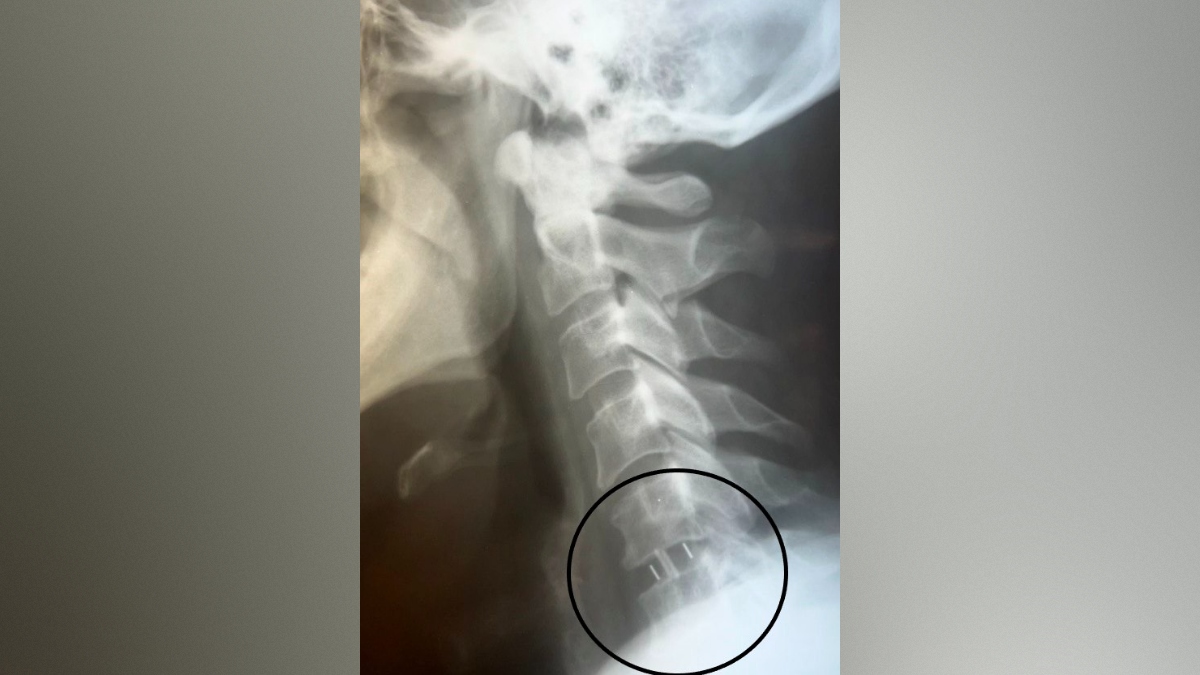

В Воронеже хирурги городской клинической больницы №11 спасли руку пациенту с грыжей. В конце октября в больницу обратился 49-летний мужчина, у которого месяц болела шея. Кроме того, пациент жаловался на онемение и слабость в правой руке. Ранее мужчина проходил лечение, но оно не помогло. Врачи обнаружили грыжу, спондилоартроз (поражение межпозвонковых суставов, которое затрагивает хрящи, костные ткани, связки и околосуставные мышцы. – Прим. ред.) и радикулит. Без удаления грыжи у пациента мог развиться паралич правой руки, поэтому было принято решение провести операцию. Об этом сообщили в пресс-службе министерства здравоохранения Воронежской области во вторник, 18 ноября.

Нейрохирурги Владимир Дронов и Евгений Дронов удалили межпозвонковый диск и грыжу с использованием операционного оптического прибора, микрохирургической техники и инструментария. Помимо этого, была устранена компрессия спинного мозга и нервных корешков, а также установлен межтеловой кейдж – металлическая конструкция, которая размещается между двумя соседними позвонками и соединяет их между собой.